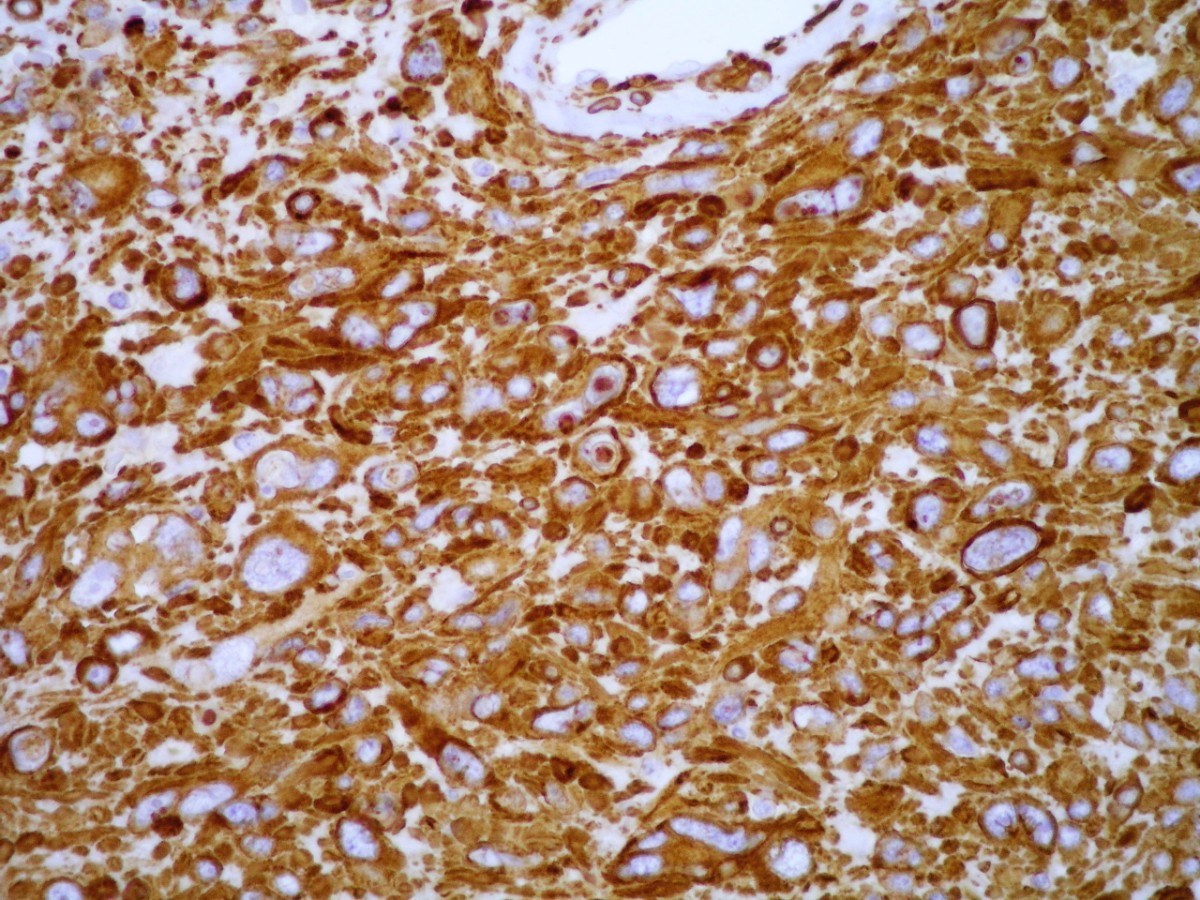

Positive stains

- Vimentin (100%), smooth muscle actin (99%), muscle specific actin (95%), calponin (80%), CD34 (32 - 53%; typically focal) (Int J Surg Pathol 2015;23:181)

- Collagen type IV, laminin (91%; pericellular), h-caldesmon (87%) (Am J Surg Pathol 2002;26:301)

Microscopic (histologic) images

Contributed by Farres Obeidin, M.D.

Case #289

Case #238